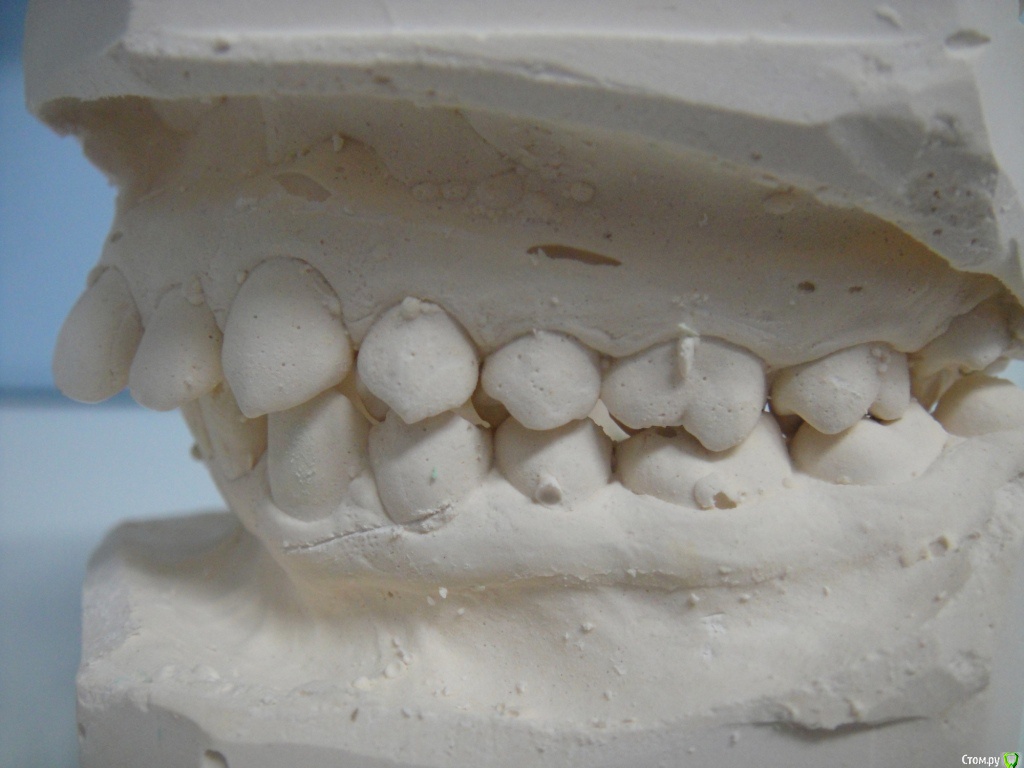

Брекеты ношу 2 месяца, мне 26 лет. Прикрепила фото открытой улыбки уже в брекетах, но так практический никогда не улыбаюсь, неудобно, (торчат два передних зуба) - "рот не открывается"  :D. Еще есть фото зубов с разных сторон, если слепков не хватит, могу добавить.

По Трг Вам однозначно необходимо удаление зубов на в.ч, а возможно и на н.ч т.к очень сильный наклон передних зубов.